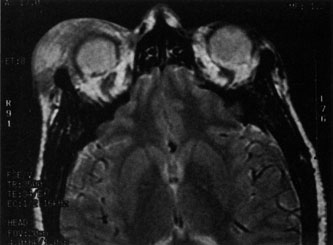

Magnetic resonance imaging (MRI) is purported to be more useful than CT in the diagnosis of preseptal cellulitis. It is less reliable at diagnosing the subtle signs of muscle enlargement and periscleritis and thus is not as useful in differentiating orbital cellulitis from other inflammatory orbital diseases.71 On MRI with gadolinium contrast, orbital cellulitis may show a smearing or linear streaking of the normal fat shadows on T2-weighted images. MRI is excellent for demonstrating localized fluid collections such as abscesses. It is not helpful in distinguishing a transudate from an exudate, because both appear liquid and are of low intensity on T1-weighted images and bright on T2-weighted images (Fig. 19).

Fig. 19. Magnetic resonance image of preseptal cellulitis with anterior abscess formation.

MRI is superior to CT in the diagnosis of cavernous sinus thrombosis. T2- and proton-weighted images show high signal luminal narrowing as well as absent flow or localized parenchymal infarcts (Fig. 20).72 Absent flow can be demonstrated as well in the superior ophthalmic vein in cases of carotid or cavernous sinus thrombosis.72 MRI with gadolinium can help define these abnormalities and can detect dural invasion.

Fig. 20. Cavernous sinus thrombosis. Axial T1 image shows cavernous carotid luminal narrowing on right and enlargement of right cavernous sinus. Note extensive sinus disease.